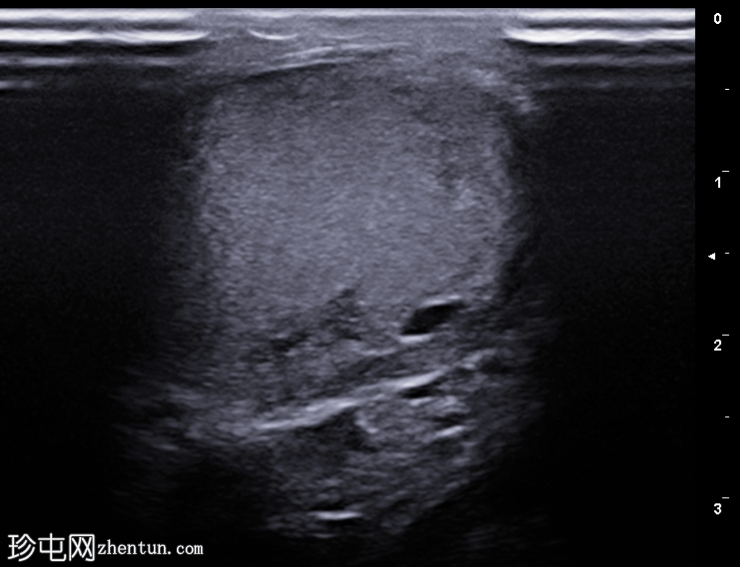

左侧阴囊

疼痛

患者的

超声

检查结果。

纵切面

右侧睾丸内可见一单房性、无回声、边界清晰的病变,囊壁薄而光滑,无彩色多普勒血流信号(未显示)。

睾丸内囊肿是良性、边界清晰的无回声病变,后方回声增强,周围包绕正常睾丸实质。大多数睾丸内囊肿无症状,位于睾丸纵隔附近。随访期间,该病变多年来保持稳定。